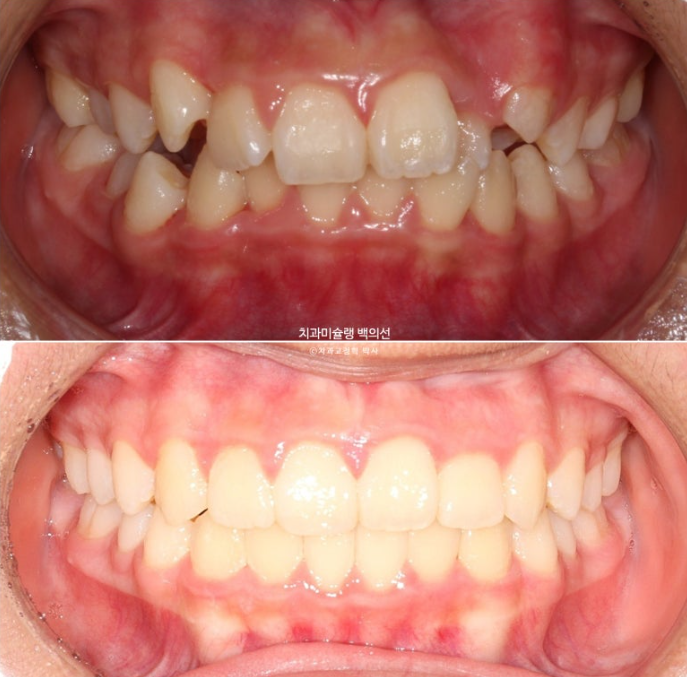

24.02~25.07

이제 전후비교 보겠습니다.

총 치료기간은 1년 6개월이며 중간에 중심선 이슈로 잠시 쉬는 시간이 4개월 있었습니다.

재제작은 총 2회 했습니다.

어긋난 중심선이 맞아졌으며 기울어진 앞니 치축도 좋아졌습니다.

앞니가 깊게 물리는 과개교합도 좋아졌습니다.